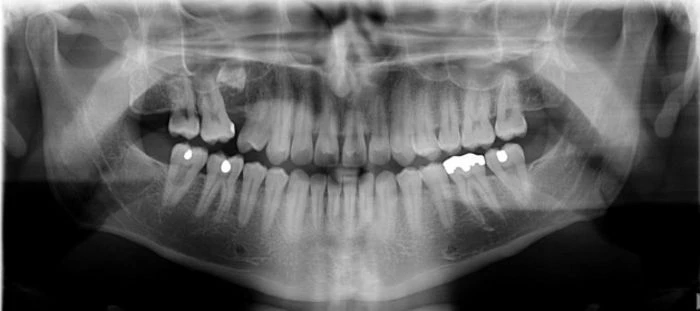

Panoramik röntgen: panoramik x-ray ya da ilk adı ile panorextir. Panoramik röntgendeki x-ışınlarının verdiği radyasyon oranı diğer yöntemlere göre daha azdır. Sonuç hızlı bir şekilde alınır. Bu yöntemde özellikle diş ağrıları olan hastalar için çok büyük zaman avantajı vardır. Panorex yani panoramik röntgen, diş doktorlarının yapacağı, diş implant ameliyatları planlamasında da çok gereklidir. Panoramik röntgen diş hekimine hastanın, burun bölgesini, sinüslerini, alt ve üst çene eklemlerini, dişlerini ve onu çevreleyen kemik yapısını gösterir. Panoramik röntgen filmi kistleri, tümörleri, kemik düzensizliklerini ve çok daha fazlasını ortaya çıkarmaktadır.